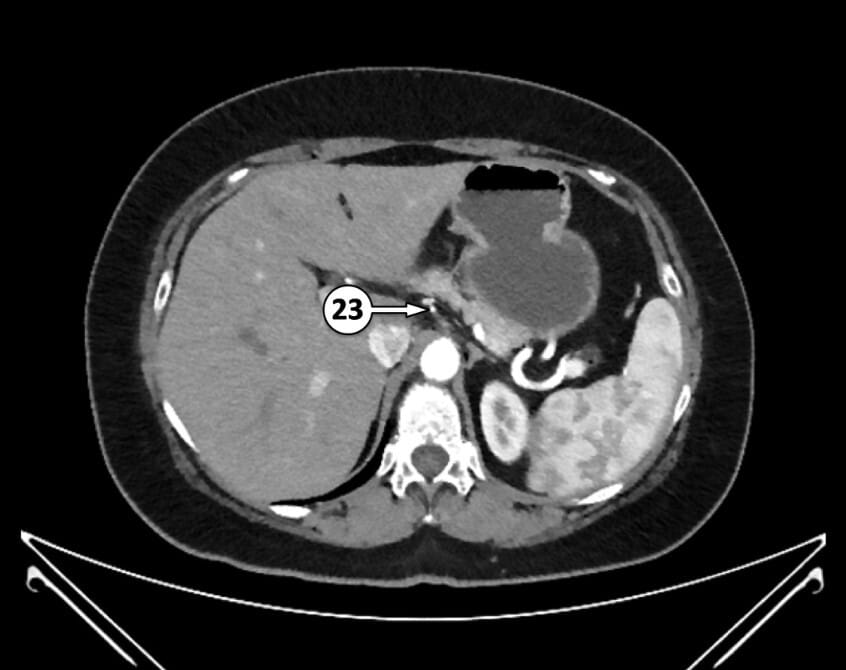

23. left gastric artery